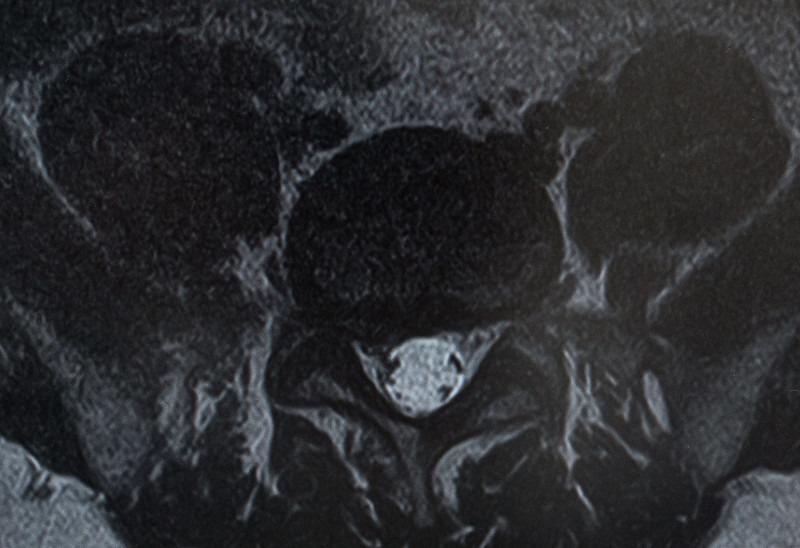

腰椎のレントゲン写真

後遺障害等級認定を申請することで、治療費とは別に損害賠償を請求することが可能です。腰椎捻挫はレントゲンやCTに移りにくく、認定を受けることが難しいといわれています。